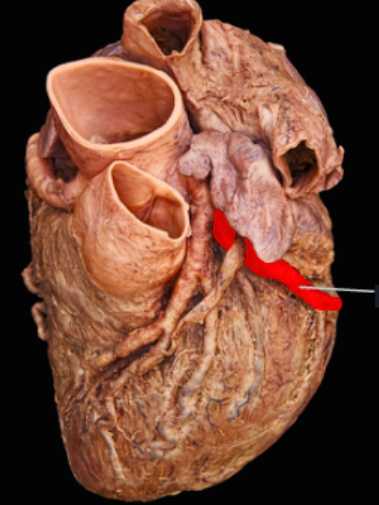

5

Q

What is this structure and what does it anastamose with?

A

Left Circumflex Branch

RCA